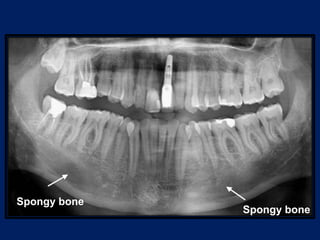

• Spongy bone: it fills the area between the cortical plates and

the alveolar bone proper.

• It contains trabaculae of bone and marrow spaces.

• Types of spongy bone (spongiosa) :-

 Type I: the trabaculae are regular and horizontal like a

ladder. This is seen most commonly in the mandible.

 Type II: irregularly arranged delicate and numerous

trabaculae. This is seen most commonly in the maxilla.

The spongy bone is very thin or absent in the anterior

regions of both the jaws.

Spongy bone

• Spongy bone:it fills the area between the cortical plates and the alveolar bone proper. • It contains trabaculae of bone and marrow spaces. • Types of spongy bone (spongiosa) :-  Type I: the trabaculae are regular and horizontal like a ladder. This is seen most commonly in the mandible.  Type II: irregularly arranged delicate and numerous trabaculae. This is seen most commonly in the maxilla. The spongy bone is very thin or absent in the anterior regions of both the jaws.